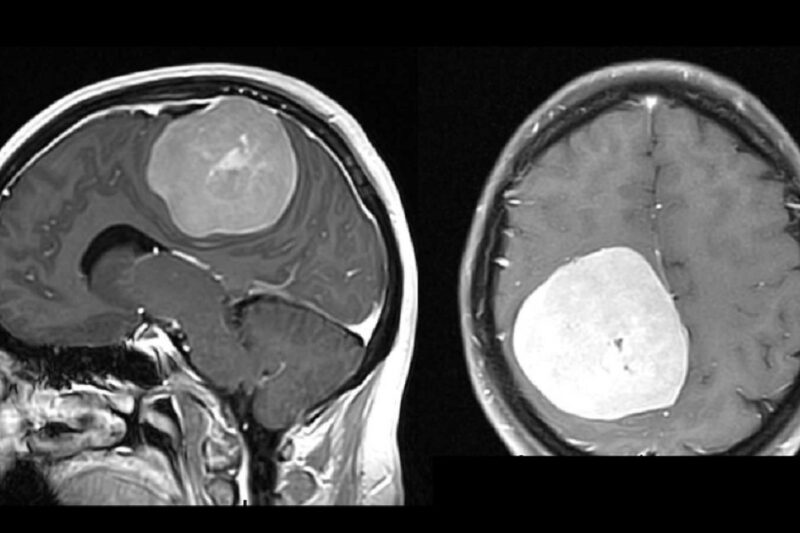

Punca Barah Otak

Punca barah otak adalah tumor otak malignan yang boleh merebak dengan cepat ke bahagian lain otak … Punca Barah OtakRead more